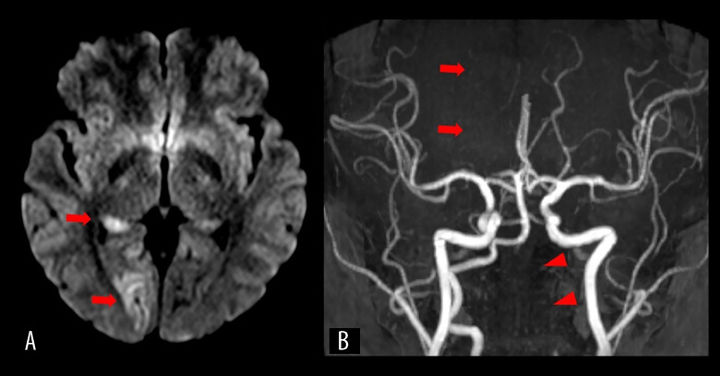

[서울=뉴시스] (사진='미국 사례 보고 저널' 캡처) *재판매 및 DB 금지

이러한 상태는 의학적으로 '척추동맥 박리증(VAD)'이라고 불리며, 의학 보고서에 따르면 매년 약 10만 명 중 1~1.5명에게 영향을 미친다. 특히 젊은 층의 뇌졸중 주요 원인 중 하나로, 자발적 요인이나 격렬한 목 움직임으로 발생할 수 있다고 전해졌다.

A씨는 곧바로 혈전 제거술과 동맥 내 혈전용해술 받았으며, 이후 이중항혈소판제 치료가 이어졌다. 치료 이후 하루 만에 증상은 크게 호전됐고, 14일 만에 퇴원할 수 있었다. 퇴원할 때는 가벼운 시야 결손만 남았다. 추적 검사에서도 혈관이 회복되는 양상이 드러났다.

18개월 후에는 시력이 크게 회복되어 가벼운 시야 결손만 남았으며, 다른 신경 기능은 완전히 회복된 것으로 알려졌다.